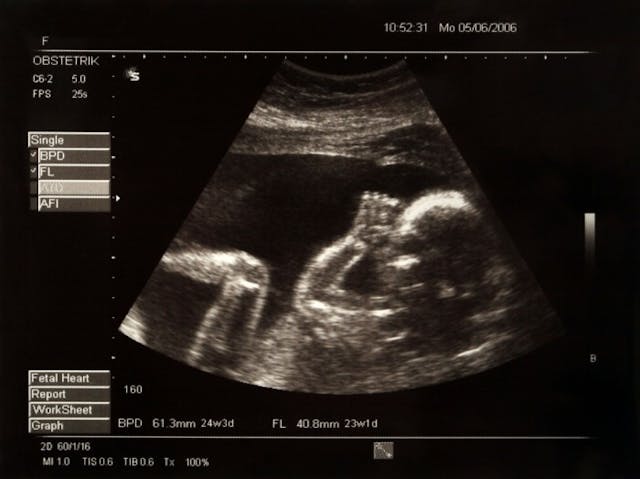

Preborn children may not be at the same developmental stage as us, but there are many things that they can still do! They have beating hearts at only 21 days gestation, detectable brain waves at roughly 42 days, and can suck their thumbs and yawn. They even have taste buds and their own fingerprints!

The incredible things preborn children can do inside the womb may surprise us, however, they certainly showcase the humanity of preborn life.